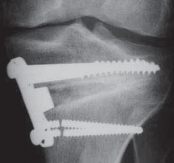

Intraoperative final AP radiograph.

C,D.

Postoperative AP and lateral radiographs.